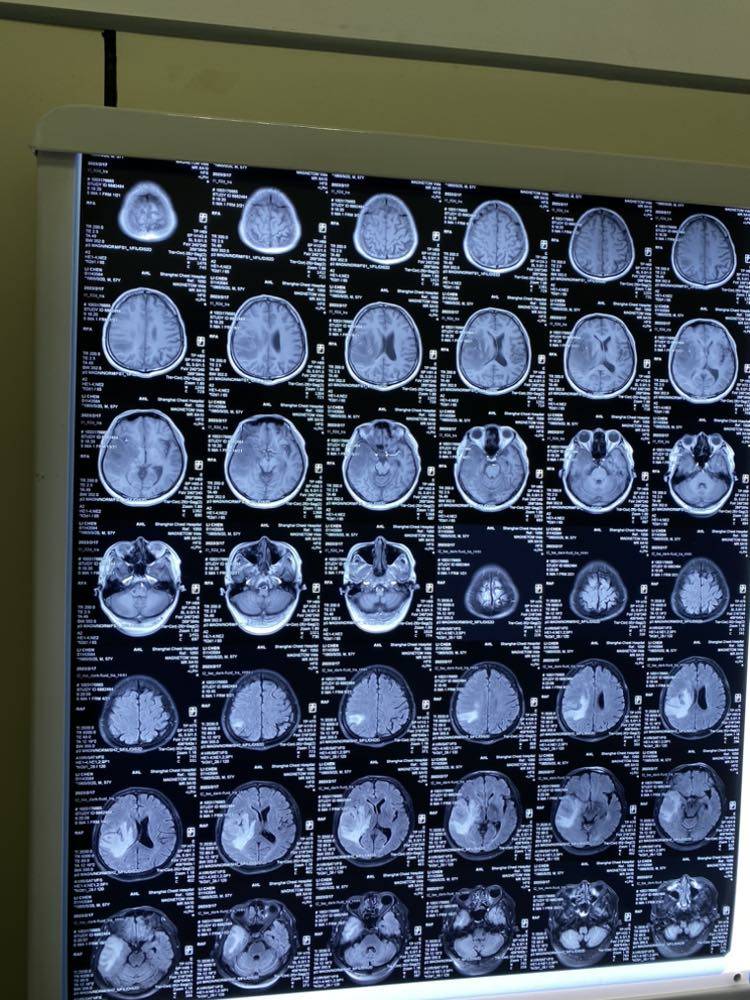

2/17定期复查,不幸我脑转了,且肿瘤长的较大4cm*3.3cm。像我们这种患有恶性肿瘤的病友,更要早发现早治疗。上一次复查是去年的7月中旬,到这次间隔了7个月,有点久了。一般来讲肿瘤三个月长一倍,如果去年10月-11月复查的话,是可以发现的,那时要比现在小一半就比较好处理了。我没有间隔三个月去复查,主要是,1,轻敌。一直以来,我恢复的都很不错,和常人无异,正常工作,正常生活!久而久之将复查的间隔拉长到了4个月。2,又赶上疫情,看病比较繁琐,又拖延了两三个月。3,没有症状。严格的来讲没有明显的症状。一般来讲,脑转会头痛,晕眩,抽搐,语言障碍,运动障碍,反应迟钝,记忆力衰退,耳鸣,视力衰退等。仔细回想一下,好像有过一次或两次耳鸣,但也只是一瞬。出门时偶尔会忘记带手机,钥匙等,但当时只是想自己年纪大了,爱忘事了。总之,不管是否有症状,都不要怕麻烦,怕花钱,坚持定期复查。切记!切记!

脑转并不可怕,早发现的话还是很好治疗的。小于3cm,一般可以用伽马刀切除(当然也要看位置),不用住院,切完马上可以回家,效果好,费用低,不易复发。像我现在这么大,就得用射波刀了,虽然技术上也不是很难,但是由于大了,照射量也要加大,风险也随之增高,可能要切5次。费用也增加了。

目前放射科医生给出初步治疗方案,局部放疗,看是否能将肿瘤缩小一点,因为位置不好,靠近脑膜,也是为了防止向脑膜转移。局部放疗后再用射波刀切除肿瘤。带具体方案定下来后,再与大家分享。